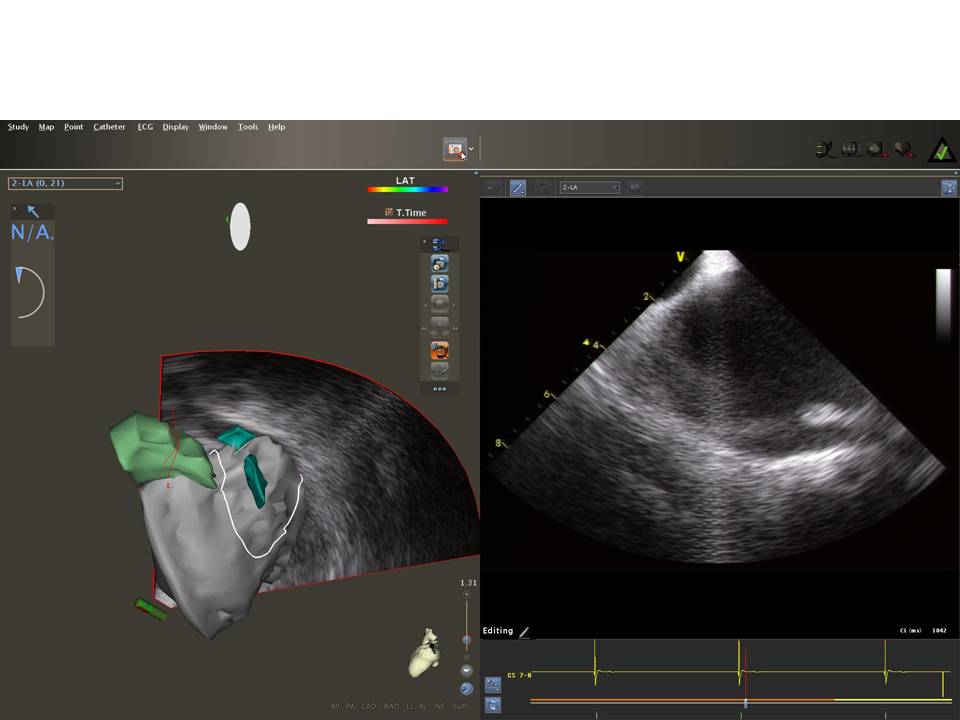

Use of ICE to Eliminate Radiation During AF Ablation

2015-07-24 13:06